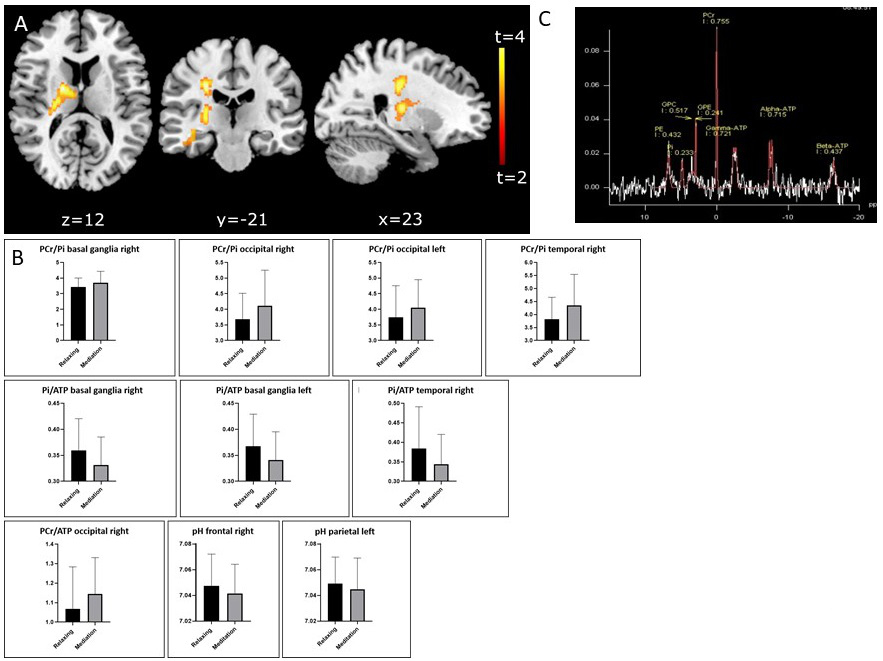

Effect of Short-Term Meditation Training on Brain Metabolism, Function and Volume

Prof. Gizewski, Dr. Steiger, Dr. Lenhart, Dr. Mangesius, Dr. Siedentopf, Dr. Pereverzyev and Dr. Galijasevic in cooperation with Prof. Singewald (LFU)

Meditation is increasingly attracting interest among neuroimaging researchers on the basis of its relevance as a cognitive enhancement technique. This longitudinal study applies a distinct and standardised meditative technique with a group of volunteers in a short-term training programme, in order to analyse brain metabolic, functional and structural changes. Initial results indicate that meditation may have considerable effects on brain energy state with different local energy management in specific brain regions and may alter cerebral grey and white matter mainly in the insula, caudate nucleus, frontal cortices, parietotemporal regions, right medial prefrontal cortex, basal ganglia and parahippocampal gyrus (Fig. 5).